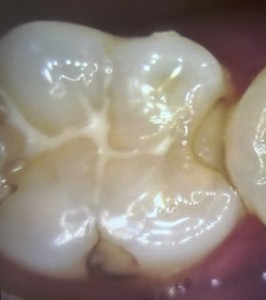

プラスチックは茶色く変色し、縁は黒ずんでいます。歯と歯の間は、凹んでいるためフロスも通しづらい状態でした。さらに詳しく調べるために口腔内エックス線も撮影し、詰め物の大きさを確認することにしました。

以上の検査から、主訴である「歯ぐき」だけではなく、「歯」も穴が空き、虫歯が進行していることがわかりました。